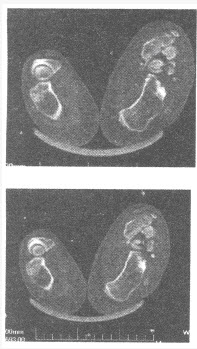

女,35岁,乏力,夜尿多。 患者所作肾上腺CT和MRI平扫及增强图像如下,考虑哪种疾病可能性大()

A:腹腔内肿大淋巴结

B:肾上腺囊肿

C:肾上腺转移瘤

D:肾上腺皮质癌

E:肾上腺腺瘤

F:肾上腺结核